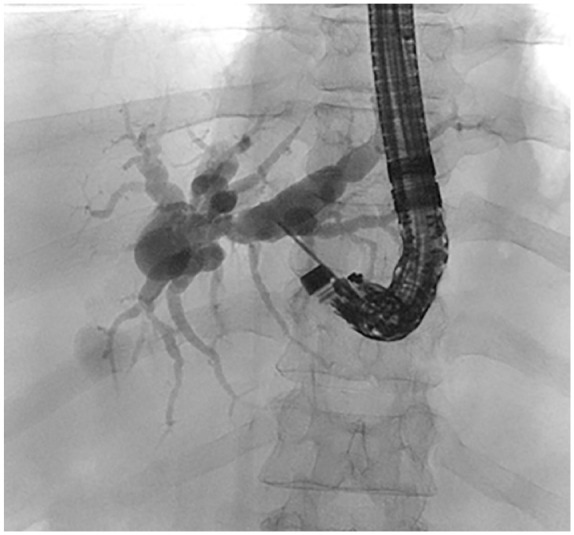

After failed biliary cannulation via standard endoscopic retrograde cholangiography approach, endoscopic-ultrasound-based rendezvous-endoscopic retrograde cholangiography (EUS-RV-ERC) is a valid alternative. One of the challenging factors in this setting is the management of the guidewire. Here, we propose a method, where a slim endoscope is used to stabilize the guidewire and optimize wire manipulation in a patient who underwent EUS-RV-ERC via a transgastric approach. This was executed in a patient suffering from severe alcoholic pancreatitis presented with a severely narrowed duodenum due to extrinsic compression and inflammation in the setting of cholangitis Tokyo Grade III.

Abstract Image